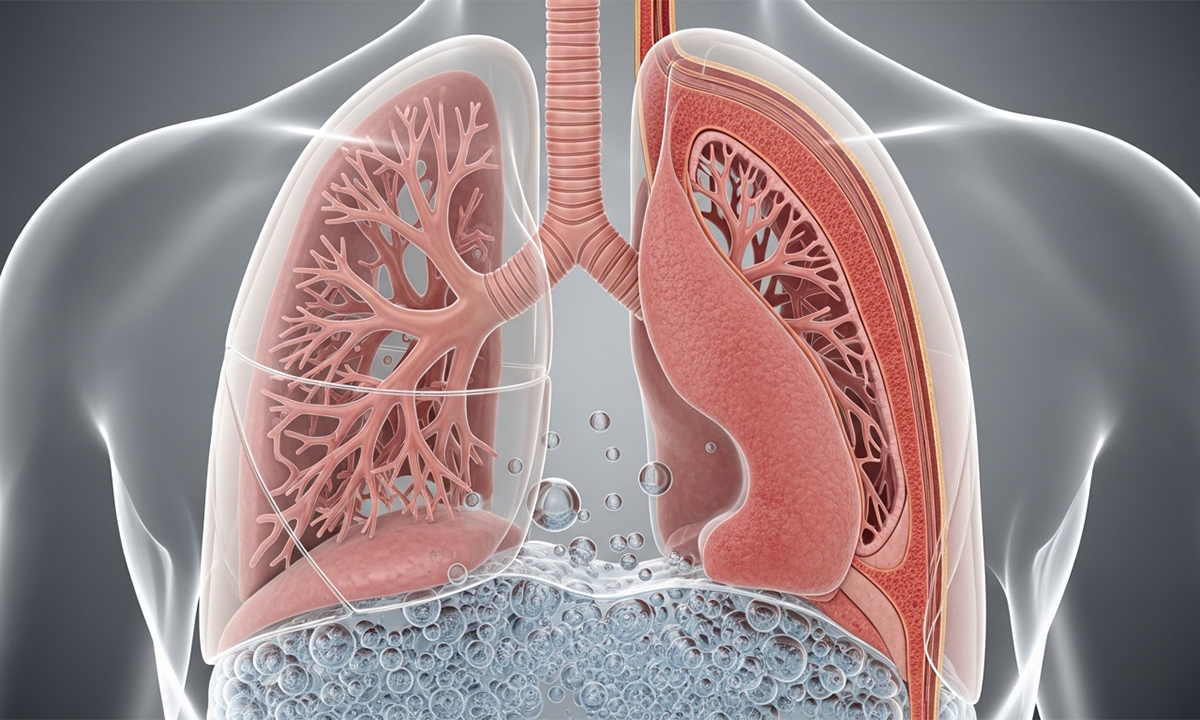

يعتبر هذا الاضطراب عدوى حادة تهاجم إحدى الرئتين أو كلتيهما مما يسبب امتلاء الأكياس الهوائية الصغيرة بالسوائل أو الصديد المزعج، وتؤدي هذه العملية الحيوية المعقدة إلى إعاقة عملية تبادل الغازات الطبيعية بداخل الجسم البشري وتسبب صعوبة بالغة في الشهيق والزفير،

وينتج عن استمرار العدوى تهيج شديد في الأنسجة الرئوية الحساسة وتضرر الأوعية الدموية الدقيقة المحيطة بالحويصلات الهوائية مما يهدف لحماية استقرار الوظائف الحيوية والفسيولوجية للأنظمة التنفسية والوعائية بالكامل.